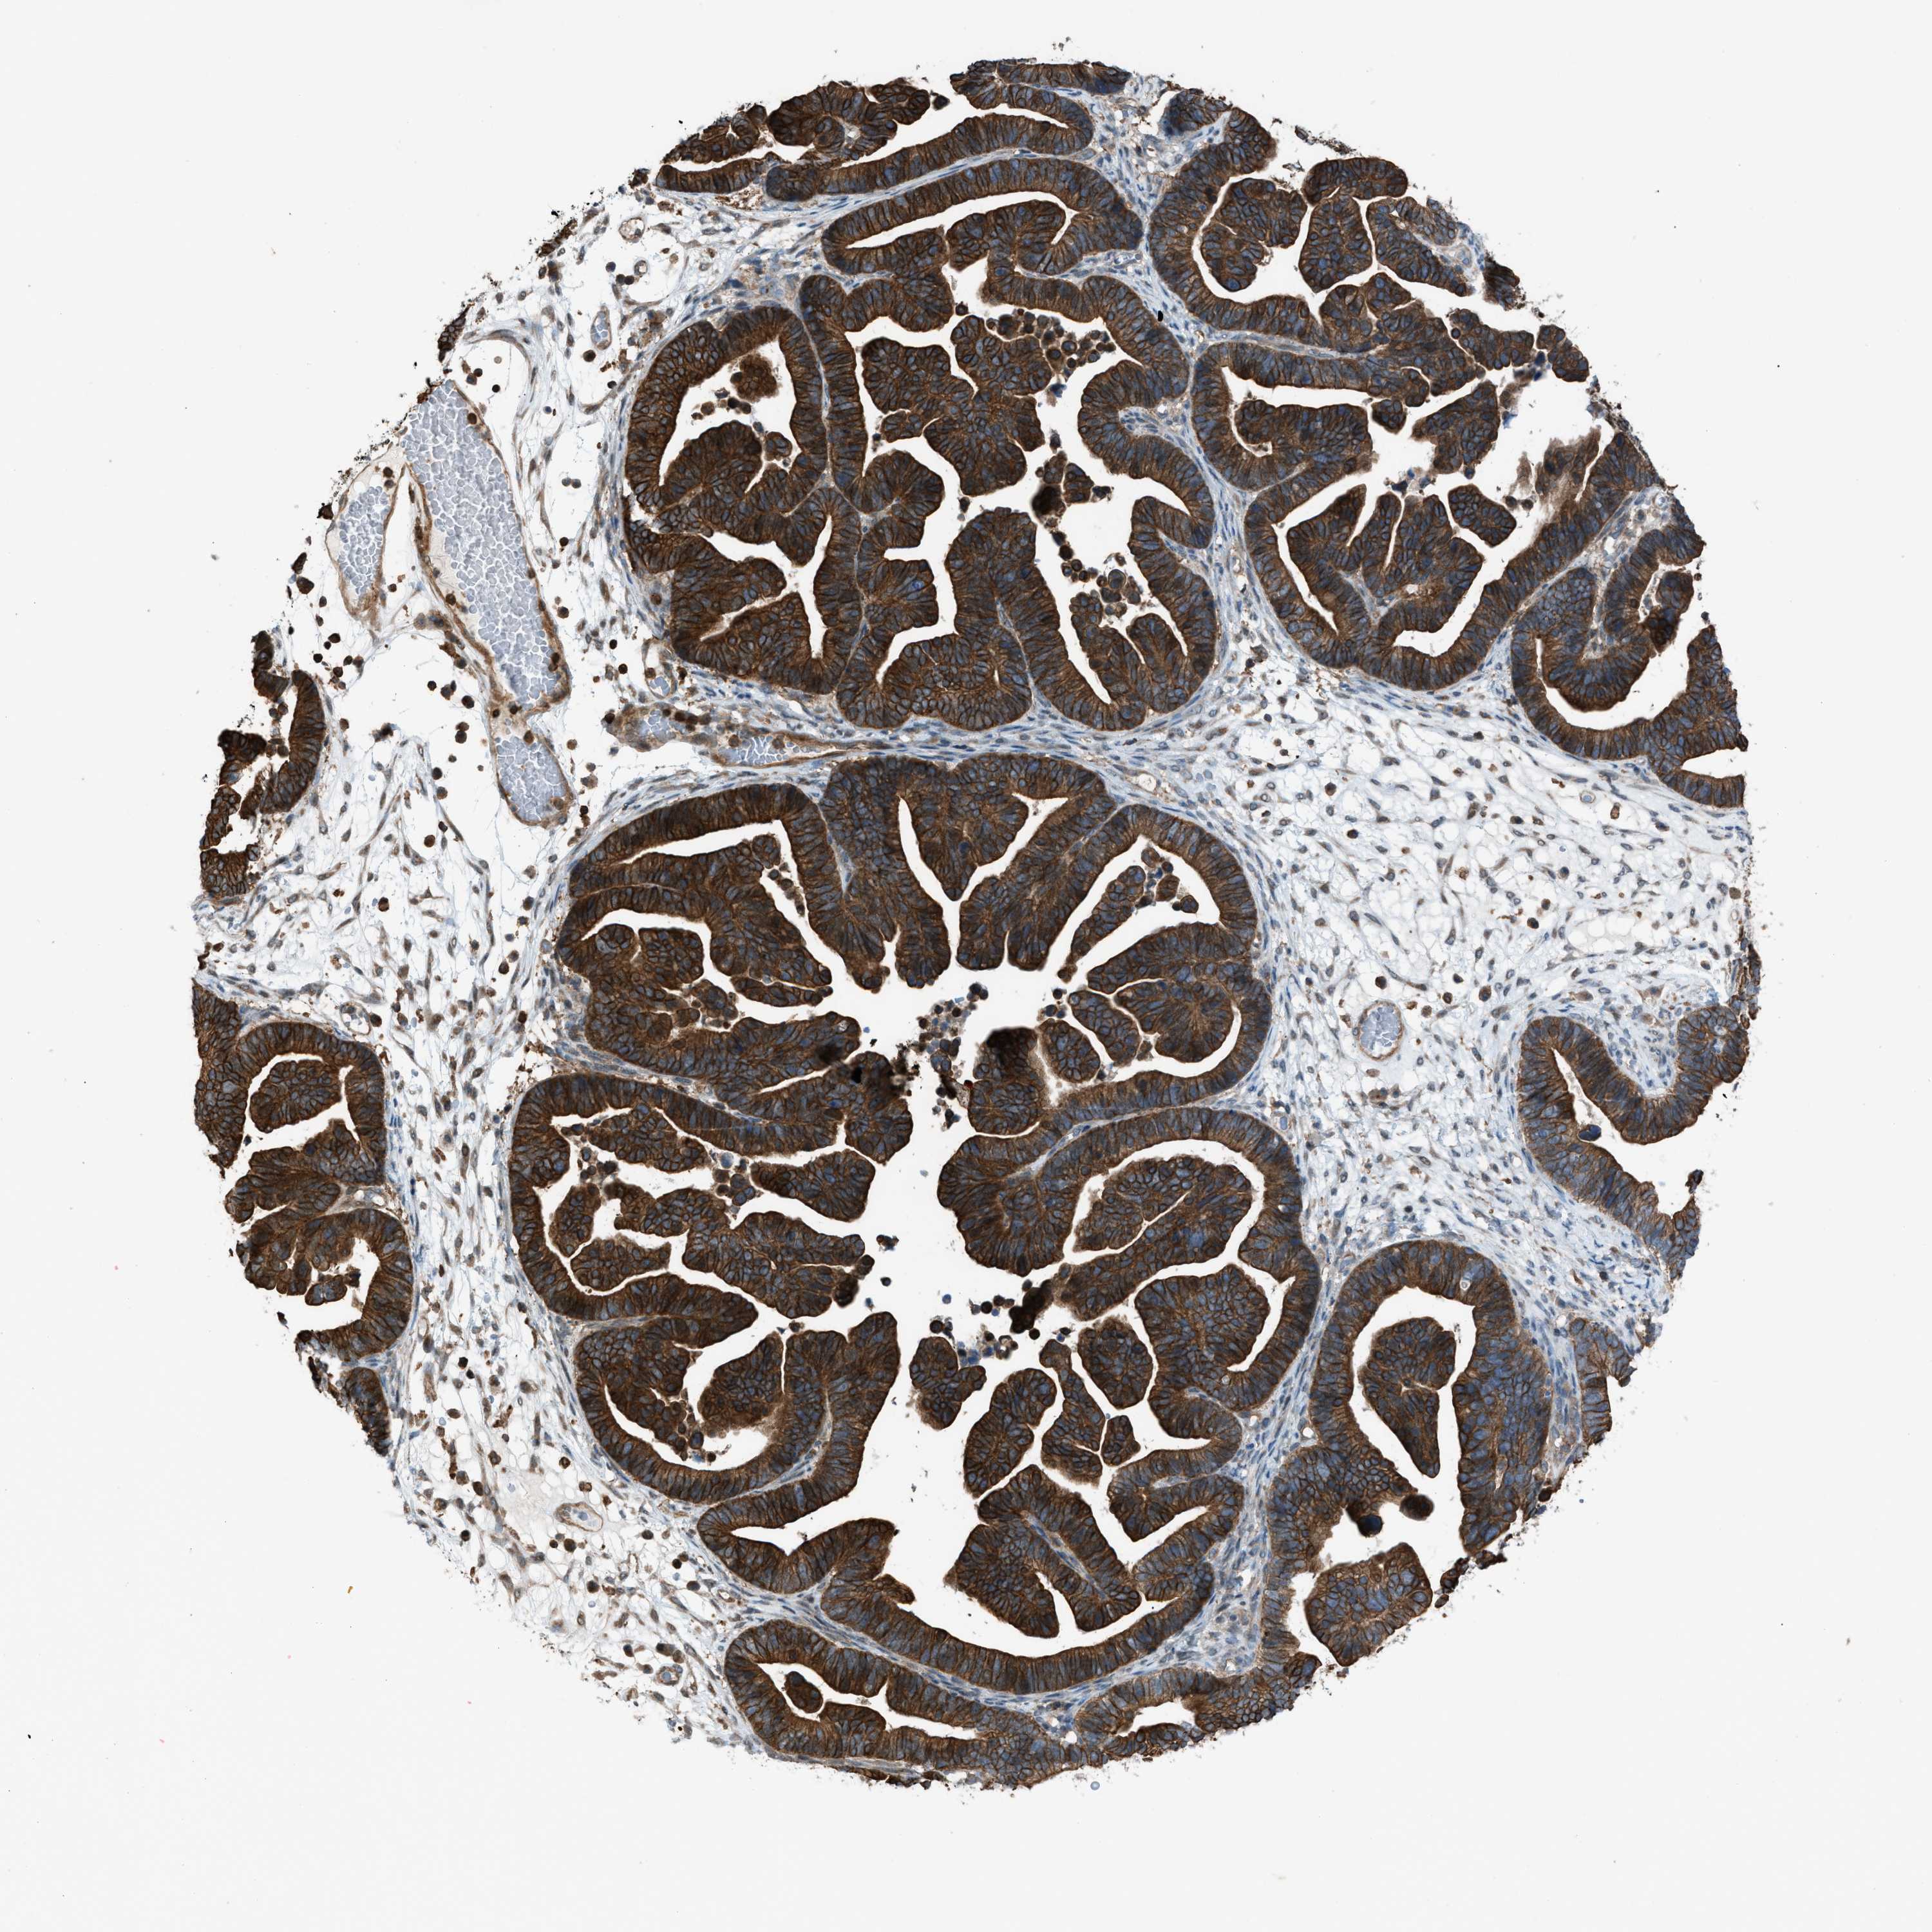

OVARIAN CANCER - Protein expressioni

A mouse-over function shows sample information and annotation data. Click on an image to view it in a full screen mode. Samples can be filtered based on level of antibody staining by selecting one or several of the following categories: high, medium, low and not detected. The assay and annotation is described here.

Note that samples used for immunohistochemistry by the Human Protein Atlas do not correspond to samples in the TCGA dataset.

Antibody stainingi

Antibody staining in the annotated cell types in the current human tissue is reported as not detected, low, medium, or high, based on conventional immunohistochemistry profiling in selected tissues. This score is based on the combination of the staining intensity and fraction of stained cells.

Each image is clickable and will lead to virtual microscopy that enables deeper exploration of all samples and also displays staining intensity scores, fraction scores and subcellular localization as well as patient and tissue information for each sample.

Antibody HPA015323

Antibody HPA015810

Cystadenocarcinoma, serous, NOS